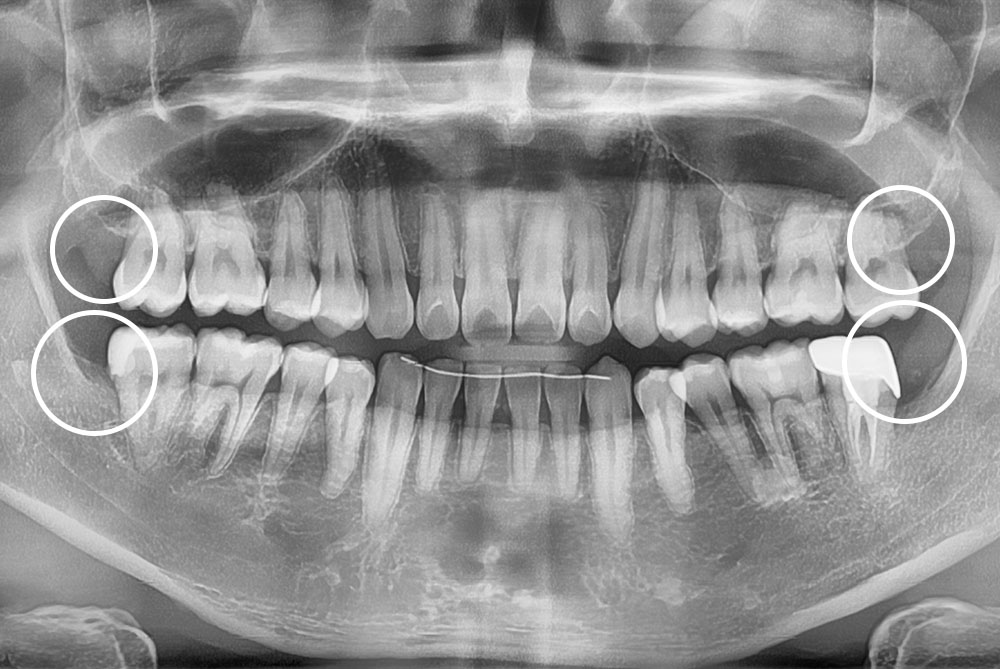

[사랑니] 매복 사랑니 발치

치료후 : 2021-08-05

세종치과는 구강악안면외과학 박사이신 원장님이 발치하는 치과입니다.